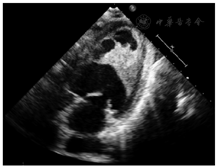

入院体格检查:血压120/70 mmHg(1 mmHg=0.133 kPa)。自主体位,双侧颈静脉未见充盈及怒张,双肺呼吸音清,未闻及干湿啰音,心界叩诊不大,心率80次/min,心音有力、律不齐、未闻及病理性杂音,双下肢无水肿。入院心电图:窦性心律,Ⅰ、Ⅱ、Ⅲ、aVF导联ST段上斜型压低约0.05 mV,aVL导联T波低平。入院诊断:嗜酸性粒细胞增多性心内膜炎。入院实验室检查:血常规示WBC 14.3×109/L,RBC 3.86×1012/L,Hb 117 g/L,红细胞压积35.0%,PLT 56×109/L,嗜中性粒细胞百分比23.7%,淋巴细胞百分比13.1%,嗜酸性粒细胞百分比58.42%,嗜酸性粒细胞8.36×109/L,嗜碱性粒细胞0.11×109/L。血沉5 mm,C反应蛋白(CRP)11.8 mg/L。心肌酶、肌钙蛋白、肾功能未见异常。复查超声心动图示(图1):LAd 50 mm,RA 50 mm×54 mm,左心室游离壁中段运动减弱,左心室腔中部至心尖部心内膜面不规则增厚,凸向心腔内,呈等高回声,其上可见纤维条索状回声附着并随心动周期摆动。左、右心房扩大,左心室内异常回声,左心室腔中部狭窄,左心室壁节段性运动异常(符合嗜酸性粒细胞增多心内膜炎超声表现)。心脏磁共振示中央段左心室内心内膜下纤维化,合并左心室血栓形成。继续给予抗凝、抗血小板、抑制心肌重构、抗感染治疗。7月12日复查血常规WBC、嗜酸性粒细胞无降低。复查便常规未见寄生虫及虫卵,排除过敏、寄生虫、家族及自身免疫等导致的嗜酸性粒细胞增多性疾病。行骨穿融合基因TEL/PDGFRB(定性)阴性,融合基因FIP1L1/PDGFRA(定性)阳性。FISH检测:PDGFα 1%(阈值<2.61%),PDGFRβ 1.2%(阈值<2.67%),FGR1 0.8%(阈值<2.07%)。免疫分型原幼细胞占1.6%,为髓系幼稚细胞。骨髓象增生明显活跃,原始细胞占0.5%,粒系占73.5%,嗜酸性粒细胞比例高达33%。骨髓活检:造血面积约占50%伴纤维组织增生(MF-2),粒系增多,以晚幼胞浆嗜酸性粒细胞为主。结合基因学检查,伴嗜酸性粒细胞增多FIP1L1/PDGFα基因阳性慢性髓系肿瘤累及心脏诊断明确。调整治疗方案给予低剂量甲磺酸伊马替尼(100 mg/d)、利伐沙班抗凝治疗,患者未诉气短不适。7月23日复查血常规:WBC 7.71×109/L,PLT 90×109/L,嗜中性粒细胞百分比83.30%,嗜酸性粒细胞绝对值0.03×109/L,嗜碱性粒细胞绝对值0.01×109/L。患者无气短不适,嗜酸粒细胞计数明显减低。病情好转出院。出院后10 d复查血常规:白细胞5.9×109/L,嗜酸性粒细胞百分比2.0%,嗜酸性粒细胞绝对值0.12×109/L。院外坚持服用伊马替尼、利伐沙班,出院后1、2个月门诊复查血常规白细胞及嗜酸粒细胞计数及比率未见明显升高。